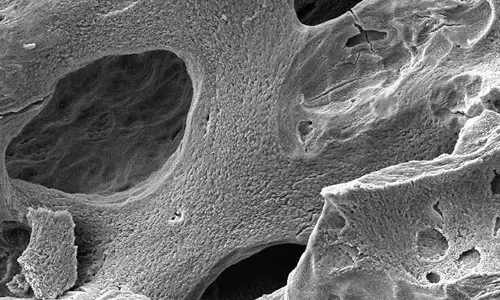

Study Reveals Astronauts Losing Bone Density For Every Month Spent In Space